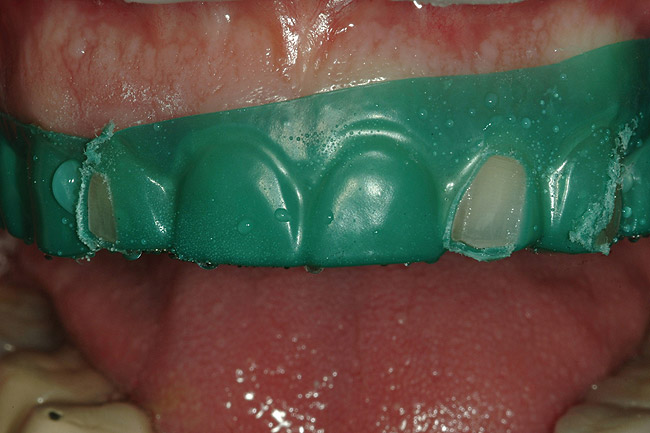

Figure 34  After isolating the preparations from moisture using a latex-free rubber dam and blue mouse, the restorations were ready to be inserted.

Figure 34